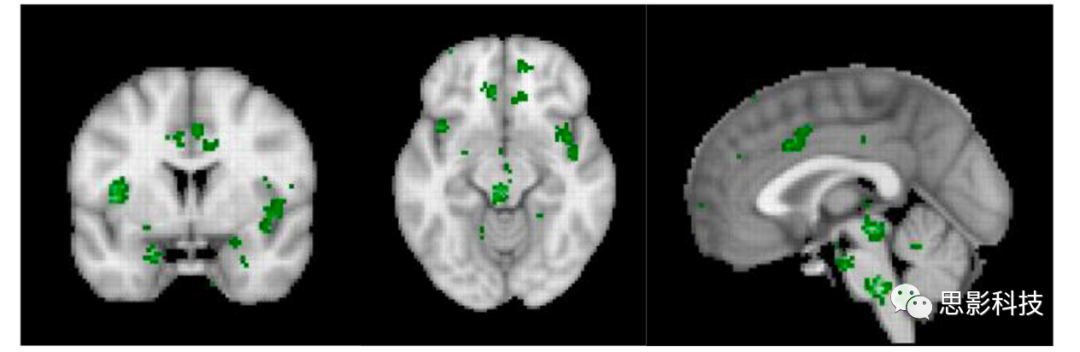

图 3. 慢性疼痛的Neurosynth元分析。前至膝下前扣带回皮层成分缺失,暗示慢性疼痛与失去的抑制有关。修改自De Ridder等人的参考文献(29)。

这一元分析进一步指出,在慢性疼痛中,前至膝下前扣带回成分的缺失可能与疼痛的持续和难以控制有关。这一发现强调了在慢性疼痛治疗中,恢复或增强抑制机制可能是一个关键方向。

使用机器学习,已经开发出了具有94%准确度的急性疼痛的fMRI神经标志(71)。神经特征包括双侧背侧后岛叶、次级体感皮层、前岛叶、腹外侧和内侧丘脑、下丘脑和背侧前扣带皮层(71),换句话说,就是侧疼痛通路和中央疼痛通路的组成部分。与神经合成元分析关于(急性)疼痛的相反,92个关于慢性疼痛的研究的相同分析并没有显示下行疼痛抑制通路中的任何活动。但侧疼痛通路和中央疼痛通路的参与仍然存在。神经合成元分析的比较明确地表明,慢性疼痛可能是由于疼痛抑制通路激活不足,而不是上行疼痛通路激活增加的结果。这与早期报告一致,即慢性疼痛与丘脑抑制丧失有关(72)(图3)。在一种广泛的慢性疼痛形式——纤维肌痛中,pgACC到rACC的不足已经得到了详细的描述(63, 73, 74)。一种类似的纯粹数据驱动的方法也识别出了具有相似准确度93%的慢性疼痛的EEG神经标志,几乎涉及相同的区域。